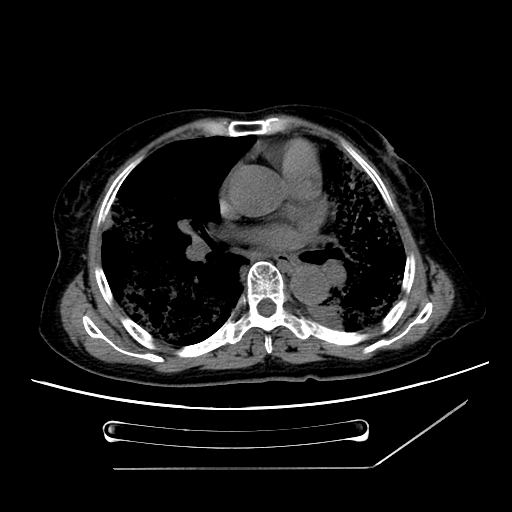

标题: CT25393:病人45岁,咳嗽,吐黄痰带血丝,发热,胸闷月余 [打印本页]

标题: CT25393:病人45岁,咳嗽,吐黄痰带血丝,发热,胸闷月余

1、左肺中央型肺癌并双肺弥漫性转移   2、双肺部感染    3、肺大泡     4、左侧胸腔积液

双侧肺弥漫性病变,可见“空泡征”及“蜂窝征”,考虑肺泡癌可能性大,左侧胸腔积液,考虑胸膜受累可能!

1)不排除肺泡癌可能。2)左侧胸腔积液。